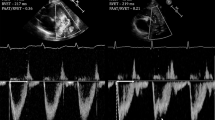

ABSTRACT.: We studied the time course and change in heart rate during respiratory pauses in puppies (3-4 wk) and young adult dogs. We measured ventilation and ventilatory pattern using barometric plethysmography and recorded the respiratory rate (RR) interval using a preprocessor with an accuracy of 0.2 ms. During tidal breathing, the fluctuations in RR interval were an order of magnitude smaller in the puppy than in the dog. During respiratory pauses in dogs, the RR interval increased sharply, stabilized around the level of expiration of previous breaths, and dropped immediately with the subsequent inspiratory effort. The time course of the change in heart rate was different in the puppy: there was a gradual increase in the RR interval during the entire course of the pause and the maximum RR interval reached was substantially higher than during expiration of previous breaths. Our results suggest that 1) the change in heart rate at the outset of respiratory pauses is too fast to be related to blood gas changes in both puppies and dogs and 2) the mechanisms responsible for the vagal gating of heart rate during tidal breathing and during respiratory pauses are not well developed in early life in the puppy.